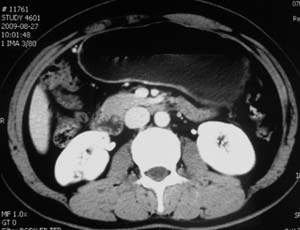

以下是引用子期在2010-3-19 20:47:00的发言:[br]血管畸形的ct增强应该有明显强化,本例并不相符合。本例双肾局部的略低密度影,累及肾盂,局部皮质明显变薄、内陷,增强扫描有轻度的强化,应考虑为炎性病变,患者为年轻男性,累及双肾的感染以结核较常见,可以没有明显的临床症状,尿中有时候也并不能查出什么;肾脓肿常有明显感染中毒症状,本例不符,另外一般的肾盂肾炎或肾小球肾炎通过小便就可确诊,其它还不能排除的是黄色肉芽肿性肾盂肾炎,然而单凭ct一般也很难鉴别。